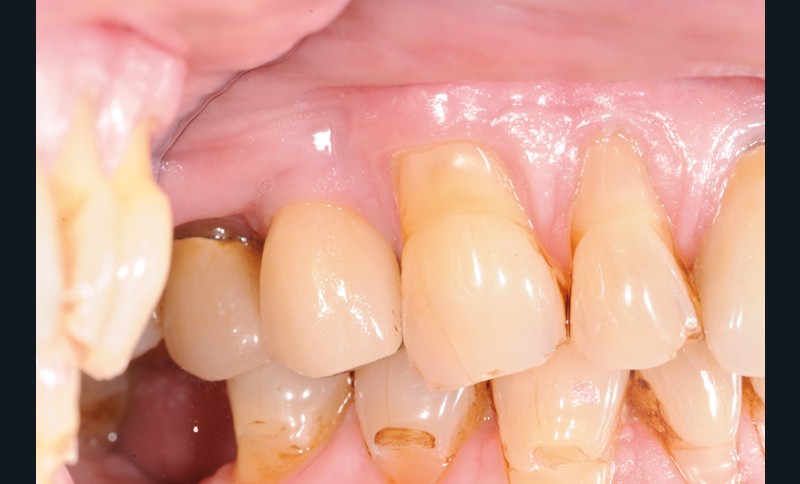

À la pose de la couronne implantaire, on notait une parfaite intégration des tissus mous(fig. 1a et b).

Lors de la maintenance de 2016, le contrôle de plaque de la patiente est toujours excellent et les tissus implantaires ne présentent pas de signes inflammatoires(fig. 2a et b).